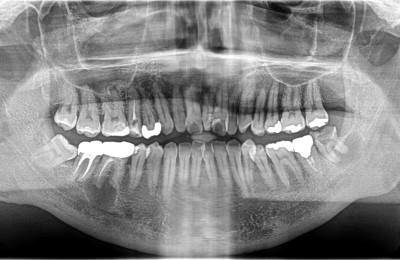

CASE02精密根管治療

-

Before

After

| 主訴 | 左右の奥歯の歯茎が腫れた。 |

|---|---|

| 治療方法 | 右下6番目、左下8番目の歯に大きな根尖病変(膿の袋)が認められる。また、右上6番目にも根尖病変、右上5番目に不良な根管充填が認められる。 ラバーダム防湿および拡大視野下にてそれぞれ精密根管治療を行った。 |

| 治療期間 | 約6ヶ月 (1歯あたり2~3回。治療後の経過観察期間も含める。) |

| リスク | 治療後、病変が再発したり治癒しなかった場合は外科処置が必要となる場合がある。 歯根破折が認められた場合は抜歯適応となる。 |

| 費用 | 110,000円(小臼歯)×1 132,000円(大臼歯)×3 ※被せ物の料金は別途88,000円×本数かかります。 |